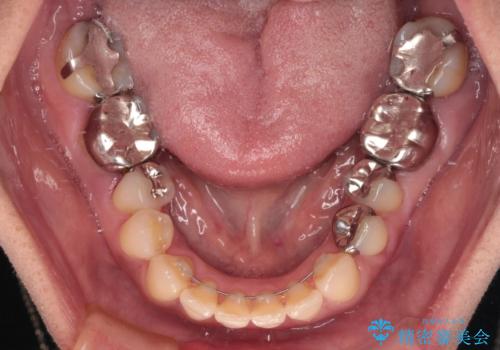

矯正治療により前歯横幅のバランスを整えた後に、上顎前歯をオールセラミックブリッジにて補綴治療を行うこととしました。

舌突出癖により、上下前歯が突出して離開してしまったため、舌のトレーニングを徹底的に行いました。